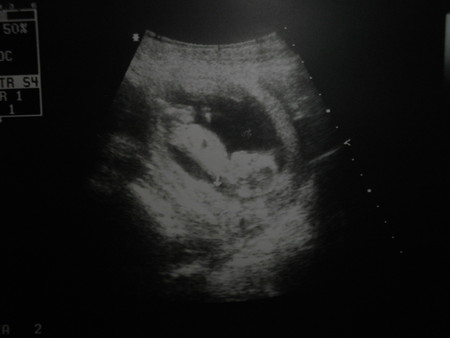

Атут 5